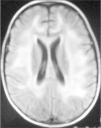

Observación ClínicaCaso 1La paciente es una niña de 7 años diagnosticada de leucemia linfoblástica aguda de alto riesgo con infiltración algodonosa en la retina en el momento del diagnóstico y normalidad del líquido cefalorraquídeo y resonancia magnética (RM) cerebral. Se inicia tratamiento con vincristina, altas dosis de metotrexato, daunorrubicina, ciclofosfamida, corticoides y triple terapia intratecal. A los 14 días apreciamos una aplasia grave medular con signos de toxicidad de grado IV en la mucosa oral, anal y vaginal, íleo paralítico con enterocolitis mucosanguinolenta y lesiones cutáneas. Comienza con deterioro neurológico progresivo, convulsiones, somnolencia y ausencia de respuesta a estímulos, con pérdida de visión. En dos ocasiones, se detecta aumento de presión arterial (PA) con cifras de 140/95. El electroencefalograma muestra ondas lentas difusas, y la RM revela áreas hiperintensas focales bilaterales, con afectación de cerebelo (figs. 1, 2 y 3). Se suspende la quimioterapia y se inicia radioterapia de globos oculares (12 Gy) y craneoespinal (18/12 Gy) por sospecha de infiltración leucémica del sistema nervioso central (SNC).

Mejora progresivamente de las alteraciones neurológicas a partir de los 7 días del inicio del cuadro, y se sospecha el diagnóstico de LEPR, que posteriormente se confirmó por la evolución. Se reinicia quimioterapia y se evita la administración de metotrexato por la radioterapia previa. Las imágenes de RM se normalizaron por completo a las 8 semanas del diagnóstico, así como la exploración neurológica, recuperando totalmente la visión. Actualmente, la niña permanece en remisión completa a los tres años de suspensión del tratamiento con un rendimiento cognitivo normal.

Ante la sospecha de LEPR, se deben realizar pruebas de imagen, en especial, RM ya que es la técnica radiológica más sensible para la demostración del edema cerebral y puede evidenciar lesiones pequeñas y focales no demostradas con la tomografía. Suele observarse alteraciones de la sustancia blanca supratentorial e infratentorial de límites poco definidos consecuencia del edema cerebral. También puede verse afectación cortical con borrado de surcos y alteraciones en otras zonas, como la afectación cerebelosa de nuestra primera paciente. La RM mostraría en secuencias T1 una señal hipointensa, y en T2, FLAIR y densidad protónica, hiperintensa. Deben incluirse imágenes de difusión de la RM, interesantes desde el punto de vista diagnóstico, pero sobre todo pronóstico, que permite distinguir el edema vasogénico del citotóxico. El edema vasogénico en región posterior es la anormalidad de imagen clásicamente descrita y se asocia a un proceso reversible con pronóstico favorable por lesiones isquémicas precoces. En contraste, la progresión del edema vasogénico a citotóxico es un hallazgo atípico e indicativo de irreversibilidad, ya que implica conversión a infarto e incluso hemorragia cerebral2,14.